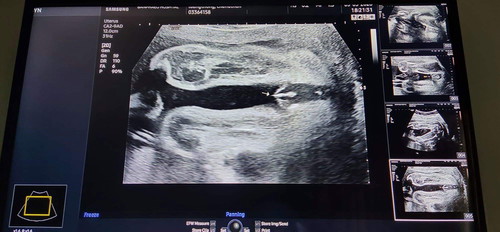

ผญ.หรือผช ค่ะแม่ๆๆ

ช่วยดูหน่อยค่ะ. ผญหรือผช. เห็นอะไรๆแหลมๆๆเลยไม่มั่นใจค่ะ

เเม่ๆพอจะดูออกไหมค่ะว่าน้องเพศหญิงหรือเพศชายค่ะ

เราเห็นเป็นกลีบนะคะ ไม่เห็นไข่ค่ะ ผู้หญิงค่ะแม่

คิดว่าผู้หญิงค่ะแม่ชัดมากไม่น่าจะเป็นผู้ชาย

ญ ค่ะ ไม่มีไข่ บ้านนี้ไข่กับจู๋ชัดมาก

น่าจะหญิง ถ้าชายน่าจะโผล่ยาวกว่านี้